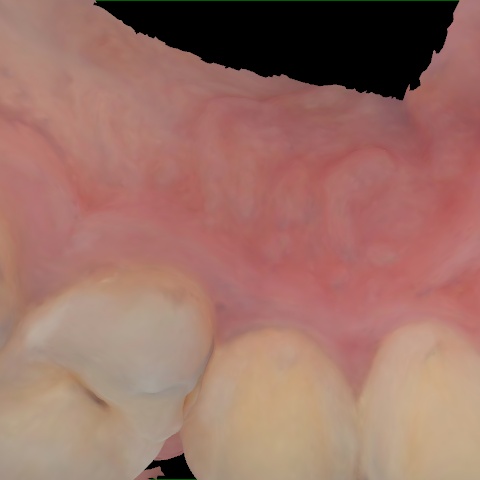

Annotated as "Good"